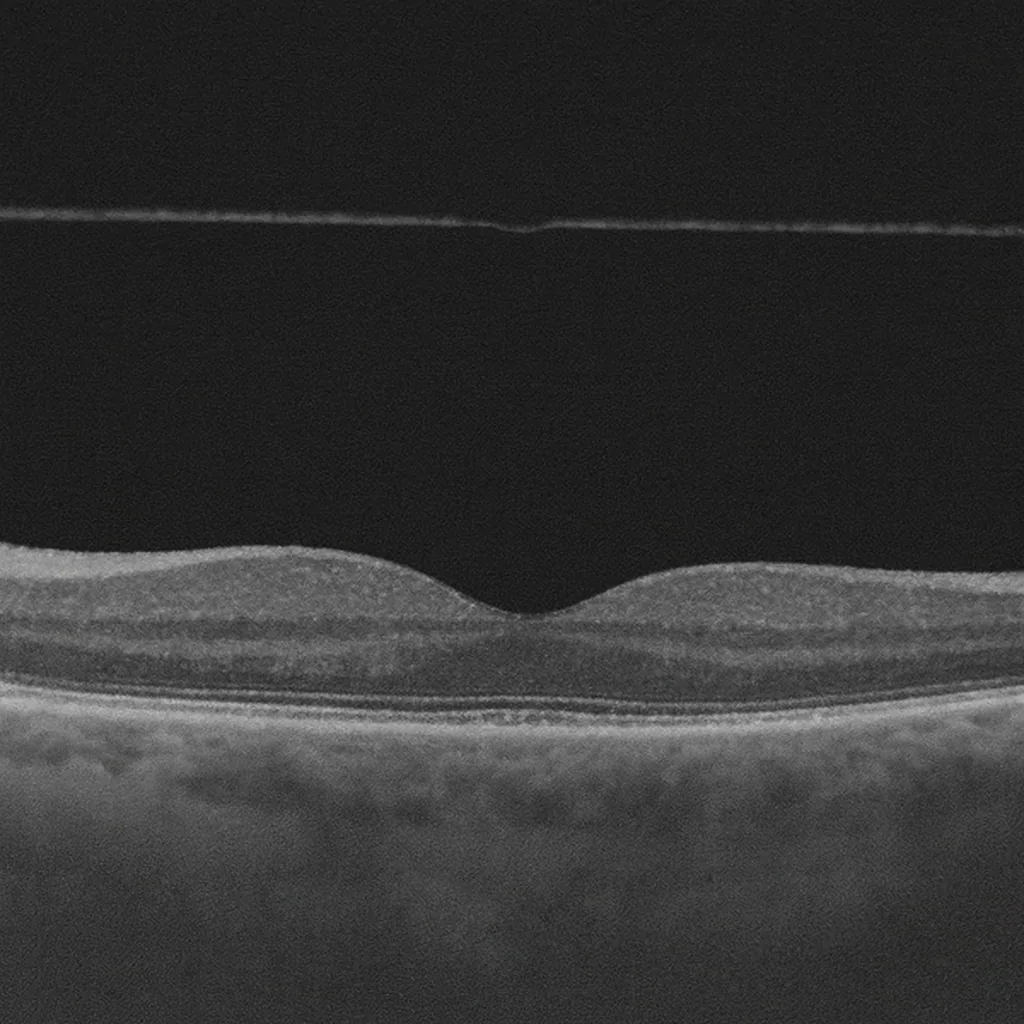

Décollement postérieur du vitré - examen fond d'œil

Posterior Vitreous Detachment — Paris Ophthalmologist

Posterior vitreous detachment (PVD) occurs when the vitreous gel separates from the retina. Common after age 50 and often benign — but it is complicated by a retinal tear in 10 to 15% of cases.